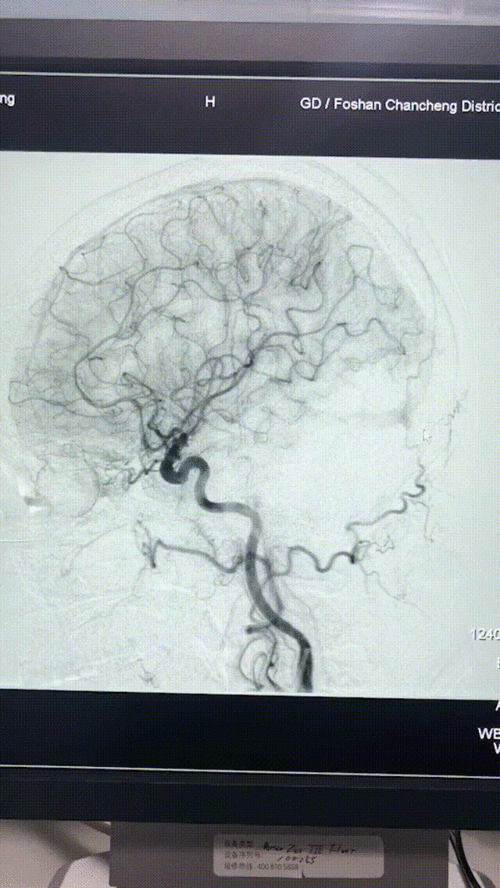

脑血管造影的三维图像